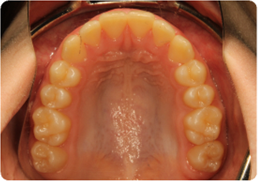

Each case shows the front view and an arch or side view, before and after BioLign Method-guided treatment.

Overlapping teeth resolved through arch form restoration